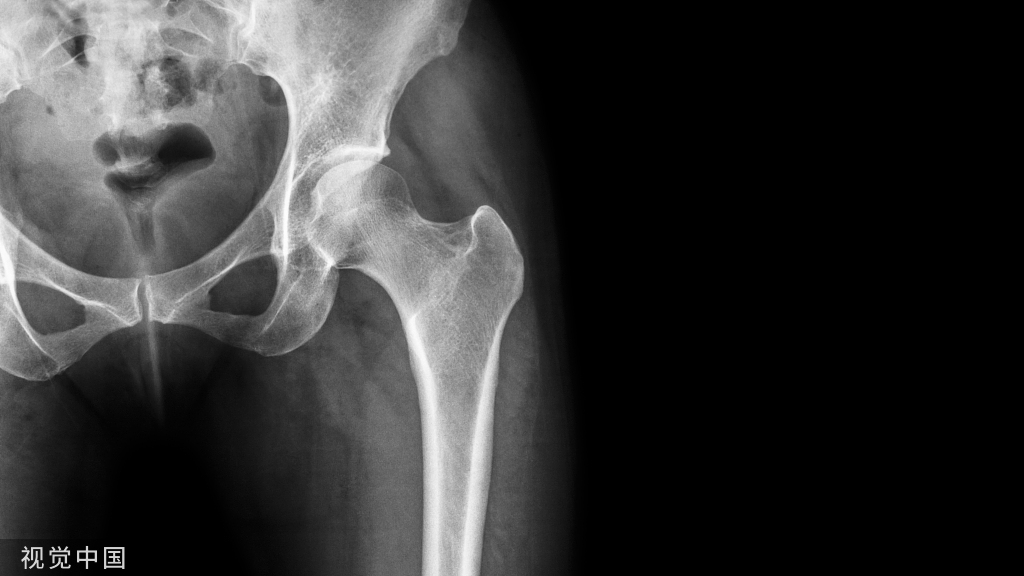

二.胫腓前韧带的生理解剖位置与Tillaux骨折的损伤机制

胫腓前韧带是指连于胫骨下端踝关节面前缘和腓骨下端前缘之间的坚韧三角形韧带。其起于胫骨前结节,止于远端腓骨前方,成45度行走,主要功能为限制下胫腓分离与腓骨外旋。

Tillaux骨折常为旋后外旋损伤所致,其发生机制是外旋应力作用在胫腓前韧带,造成胫骨远端前外侧骺板撕脱性损伤。这种骨折多发生在内侧的骺板已经闭合,但骺板的外侧尚未闭合的特定时期,也就是女性12~14岁,男性14~17岁期间,胫骨远端骨骺闭合的整个过程大约历时 18 个月,闭合的过程中,骺板的中央部分首先闭合,其次是前内侧,然后是内、后侧,最后是外侧。闭合和未闭合骨骺的强度不同,这是影响其骨折线走行模式的重要因素。